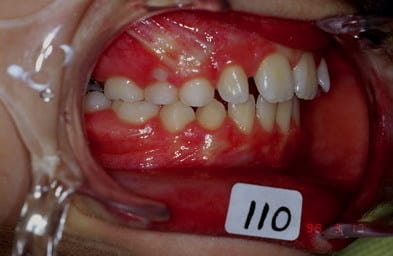

cas n 2

classe II 1 avec pouce

QH + Ecran cuccal pendant 4 mois seulement separent les photos